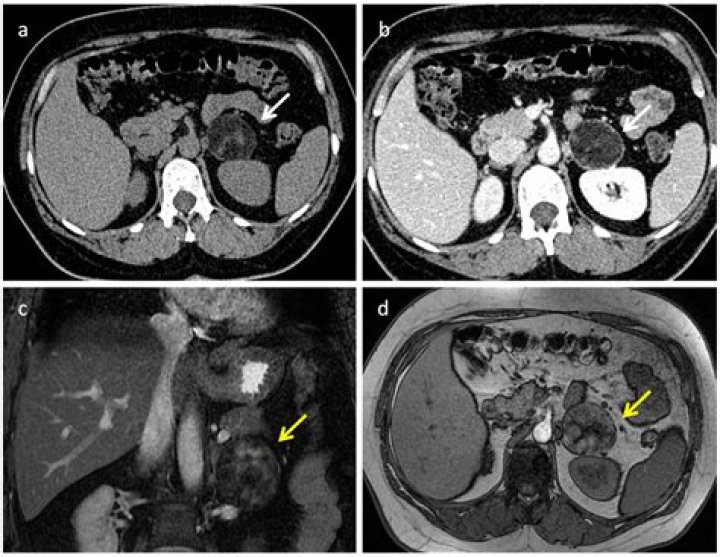

The ESE/ENSAT guidelines recommend a single follow-up test (non-contrast CT or magnetic resonance imaging) after 6 to 12 months for adrenal masses larger than 4 cm at diagnosis, or for adrenal masses with indeterminate characteristics, to exclude significant growth [2].